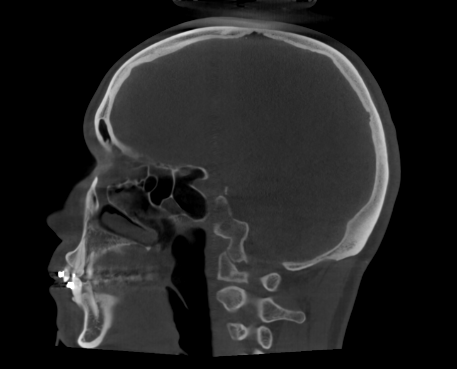

Imagen 2: Vista sagital de CBCT de cráneo completo para cirugía ortognática (FOV 23×26). Imagen aportada por RD3D.

El CBCT 3D permite obtener una imagen tridimensional completa del esqueleto facial, ofreciendo información milimétrica sobre la posición de huesos, dientes y articulaciones.

- Reconstrucciones 3D realistas del cráneo y la mandíbula.

- Evaluación de asimetrías faciales y relación entre maxilares.